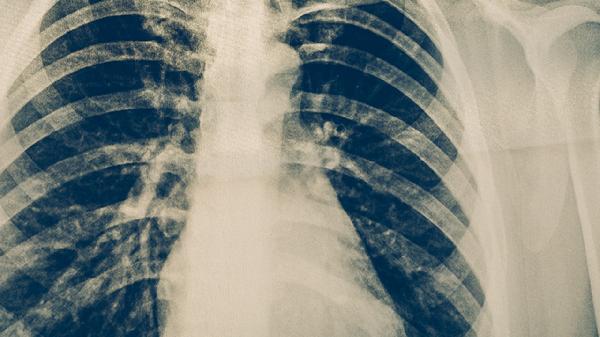

肺部少量積液是否嚴(yán)重需結(jié)合病因判斷,多數(shù)情況下不嚴(yán)重,但少數(shù)可能提示潛在疾病。肺部積液又稱胸腔積液,指液體異常積聚在胸膜腔,少量通常指影像學(xué)檢查顯示液深小于10毫米或未淹沒肋膈角。

生理性少量積液可能由心力衰竭代償期、低蛋白血癥或月經(jīng)期激素波動(dòng)引起,通常無明顯癥狀且可自行吸收。這類情況無須特殊治療,建議定期復(fù)查胸部超聲或X線,觀察積液變化。日常注意限制鈉鹽攝入,避免劇烈運(yùn)動(dòng)加重心肺負(fù)擔(dān),適當(dāng)補(bǔ)充優(yōu)質(zhì)蛋白有助于促進(jìn)液體回吸收。

病理性少量積液需警惕結(jié)核性胸膜炎、早期肺癌胸膜轉(zhuǎn)移或系統(tǒng)性紅斑狼瘡等自身免疫疾病。結(jié)核性胸膜炎常伴隨午后低熱、盜汗,胸膜轉(zhuǎn)移可能伴有咯血、消瘦,此時(shí)積液雖少但屬于嚴(yán)重疾病的征兆。需通過胸腔穿刺化驗(yàn)積液性質(zhì),必要時(shí)行胸膜活檢明確診斷。結(jié)核性胸膜炎需規(guī)范使用異煙肼片、利福平膠囊、吡嗪酰胺片等抗結(jié)核藥物,惡性腫瘤需根據(jù)分期選擇化療或靶向治療。

出現(xiàn)不明原因咳嗽、活動(dòng)后氣促或胸痛時(shí),建議盡早就醫(yī)完善胸部CT、腫瘤標(biāo)志物等檢查。日常避免吸煙及接觸粉塵,保持環(huán)境通風(fēng),睡眠時(shí)可墊高床頭減少夜間呼吸困難。若積液量增加或出現(xiàn)發(fā)熱等感染征象,需立即就診調(diào)整治療方案。